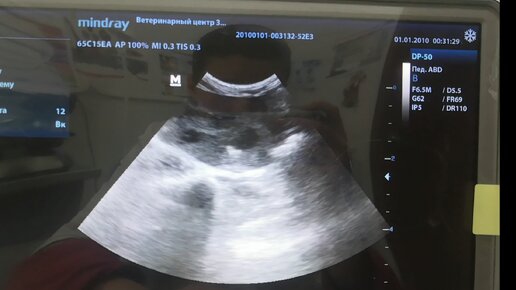

Йоркширский терьер Пряник, кобель, крипторх 9 лет. Поступил на приём к коллеге с жалобой на кровь в моче, отказ от корма и воды в течении двух дней. Началось с желудочно-кишечного расстройства, общее состояние не удовлетворительное, температура субфебрильная. Во время осмотра из препуция было выделение бурого цвета с гноем. Были взяты анализы крови и на пироплазмоз. Проведена инфузионная терапия и антибиотикотерапия. Ко мне был направлен на УЗИ. К моменту приема пришли результаты крови. По словам владельца самочувствие улучшилось, вечером поел...